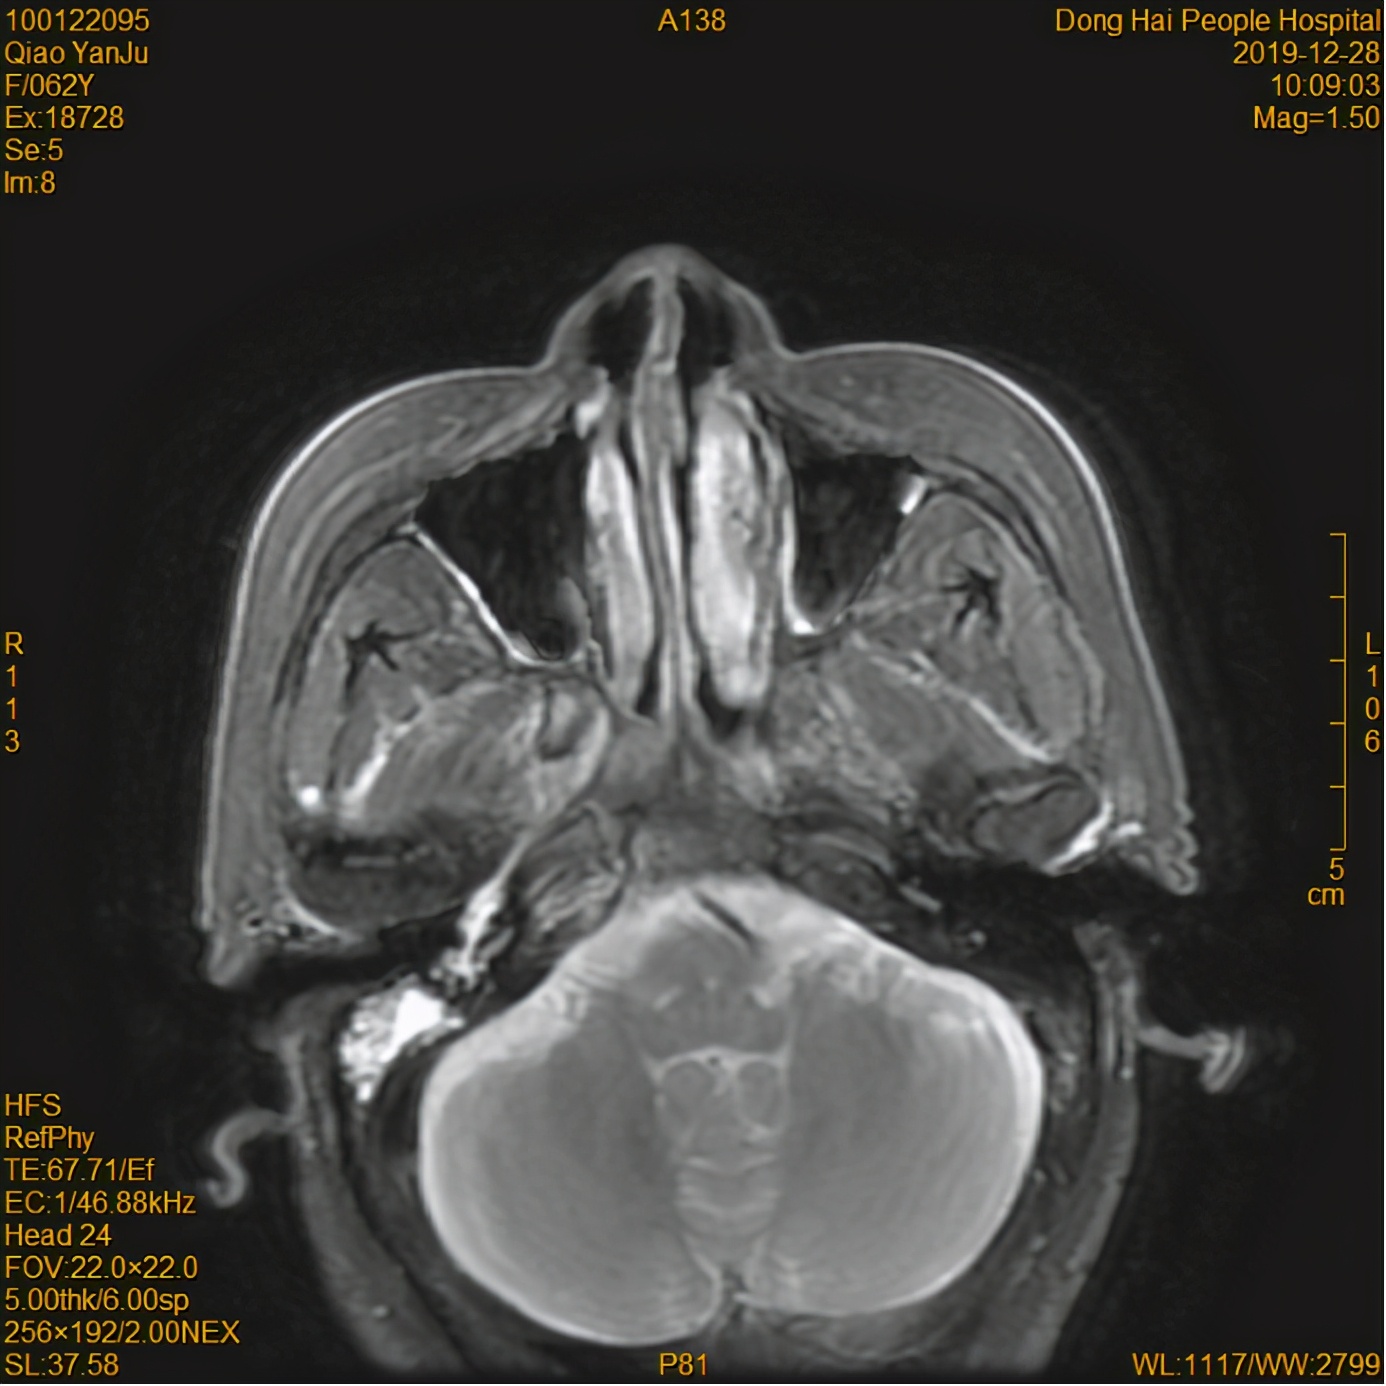

放疗前

经过8个月的放疗后,乔某鼻咽部肿瘤、颈部淋巴结退缩明显,多次复诊肿瘤控制较好。乔某的家人也松了一口气,发现放疗的效果确实好,而且人也不至于那么痛苦。